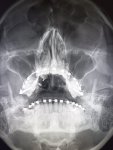

Здравствуй двачик, на прошлой неделе вышел из отпуска и уже дергается глазик, вчера сидел на работке пока поликлинику не закрыли и не все доделал. Не могу перестать кричать внутри головы! Потому мы с вами будем сегодня играть в доктора! Я буду вам показывать фоточки а вы угадывать пиздецомы! Што шпогнали! Найдите поломку!